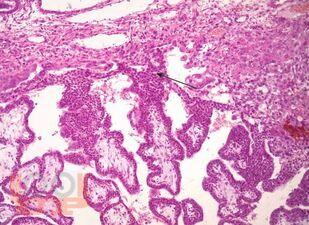

В монографии изложены современные представления об этиологии, патогенезе заболеваний беременности, родов и послеродового периода, патоморфологических изменениях в органах и тканях при акушерских заболеваниях и экстрагенитальных нозологиях, являющихся ведущими в структуре материнской смертности; представлены особенности патологоанатомического исследования и формулирования патологоанатомического диагноза при материнской смерти.